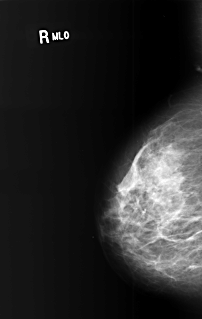

B_3400_1.RIGHT_MLO

RIGHT_CC LINES 5912 PIXELS_PER_LINE 3720 BITS_PER_PIXEL 12 RESOLUTION 50 NON_OVERLAY

RIGHT_MLO LINES 5104 PIXELS_PER_LINE 3232 BITS_PER_PIXEL 12 RESOLUTION 50 NON_OVERLAY